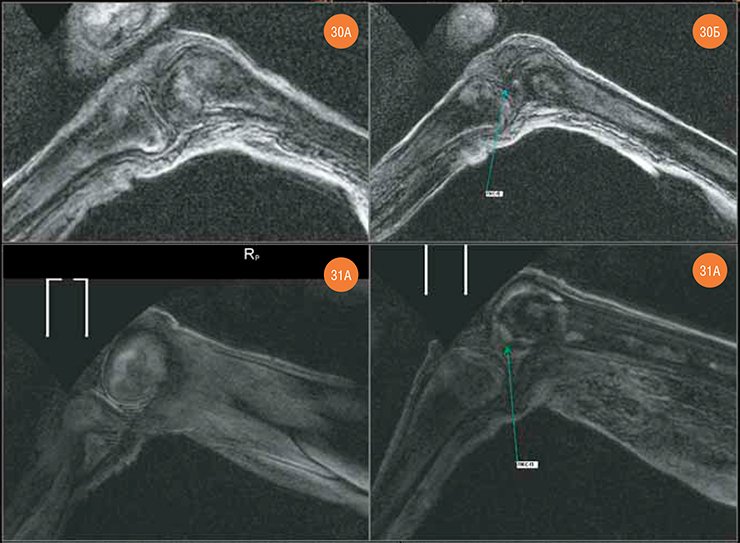

컴퓨터 단층촬영을 한 결과 얼음공주도 왼쪽과 오른쪽의 무릎에 이상이 있음이 밝혀졌다(레탸긴, 사벨로프, 2014, 그림1)

그림 1. 아크 알라하 3유적의 1호분, 얼음공주의 무릎. 윗 줄은 왼쪽무릎관절이고 아랫줄은 오른쪽 무릎관절인데 현저하게 차이가 있다. 왼쪽무릎관절30A-좌골 경골에서 연골 아래에 경화증 및 부종발견. 30B-전방십대인자가 거의 들어남(화살표) 오른쪽무릎관절31A-많이 남은 반원상의 연골, 31B-전방십대인자 변형되고 두텁지만 모습은 어느정도 유지되고 있음(레탸긴, 사벨로프, 2014).